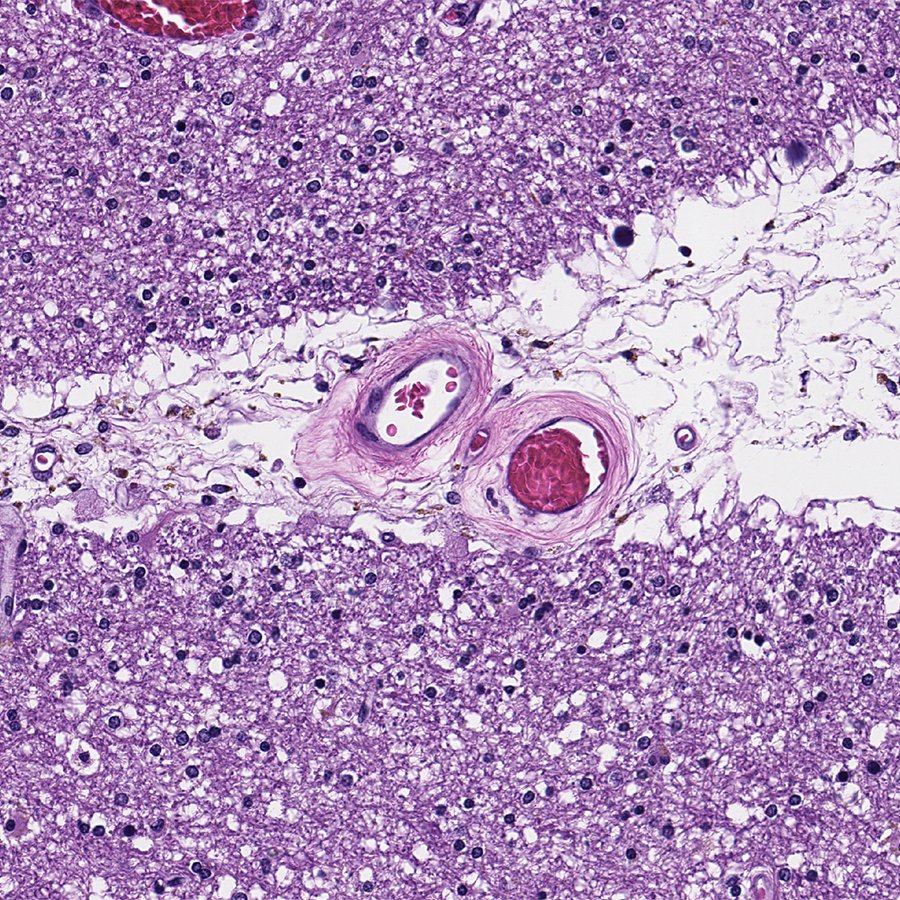

This is subcortical arteriosclerotic encephalopathy, a.k.a. Binswanger's Disease. Resembles

#Alzheimers clinically, but it's caused by bad#arteries.#Exercise and healthy diet are your best protection!#pathology#neuropath#pathtwitterpic.twitter.com/bgE5j6hV8y